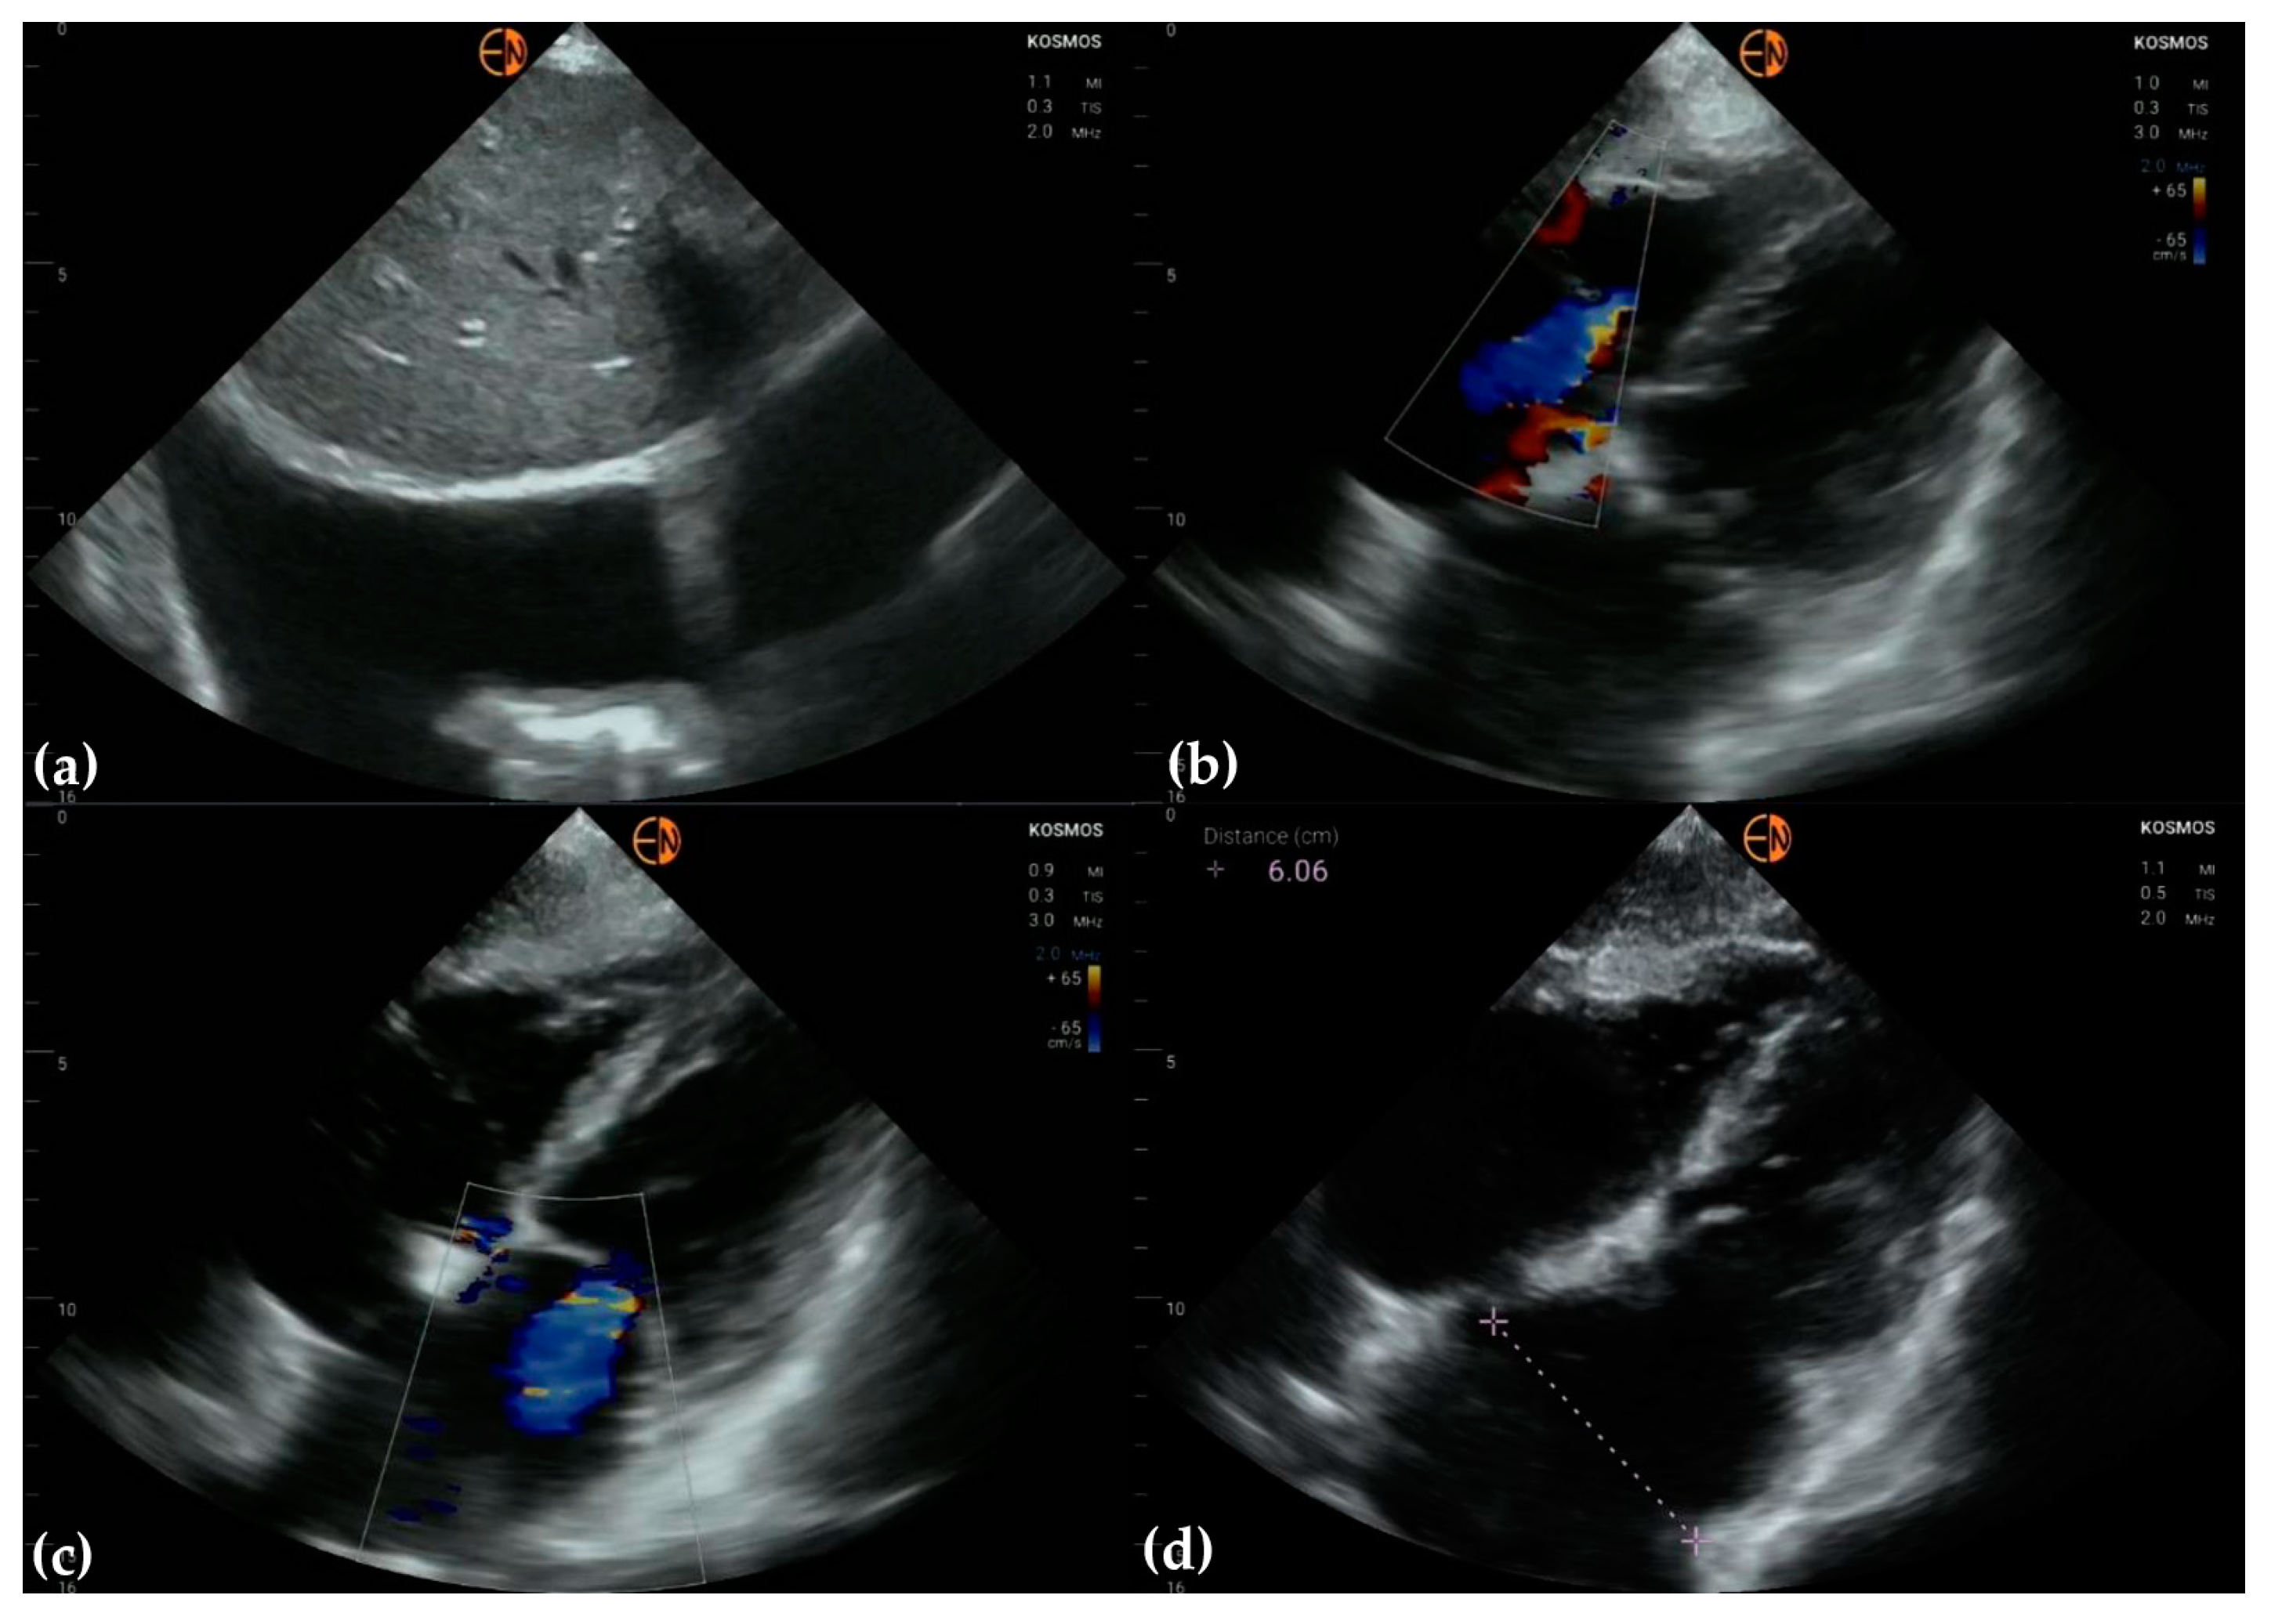

3.3. Valvular Stenosis and Regurgitation

3.4. Other Findings